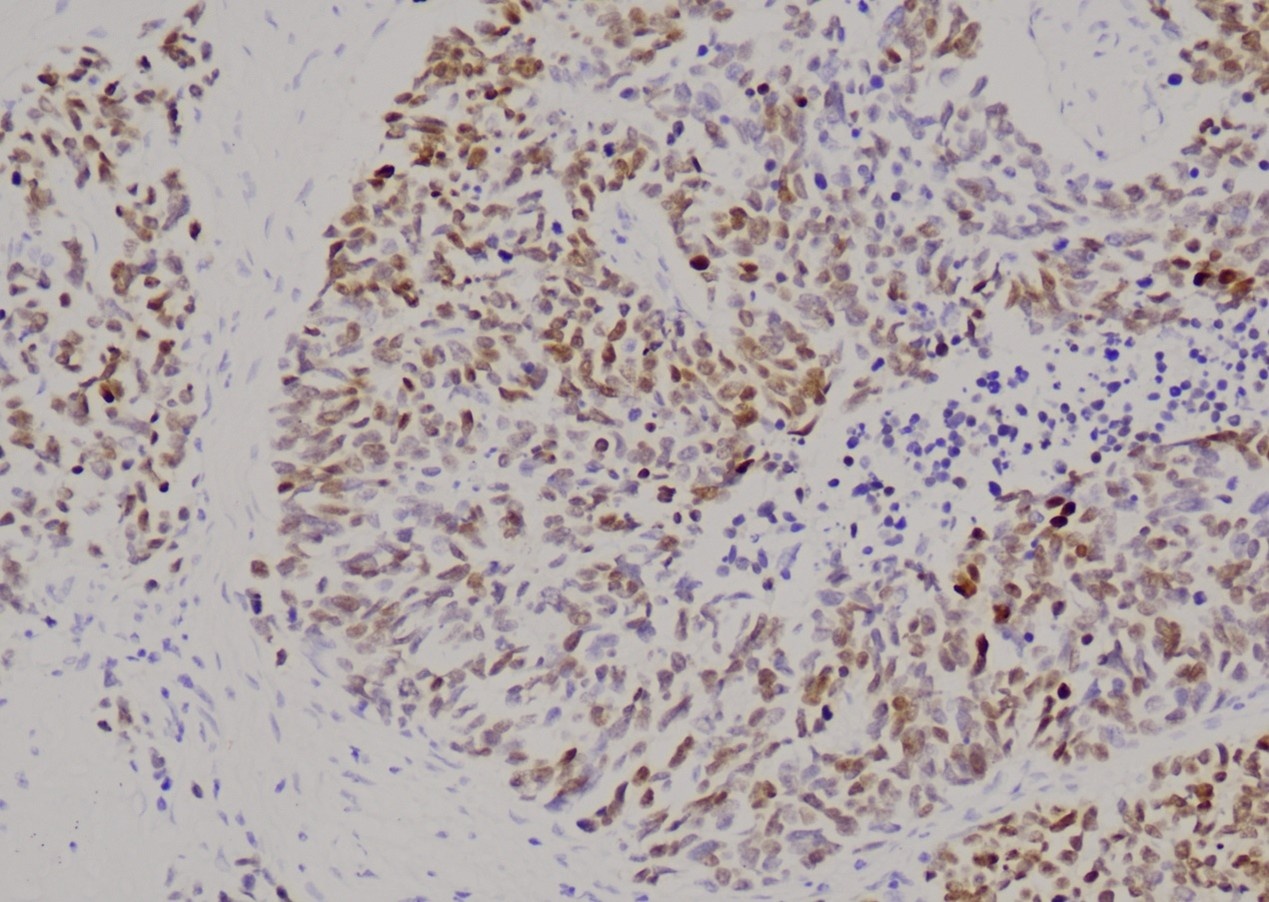

NF(Neurofilament,神经丝蛋白)是神经元特异性中间丝蛋白,由三个亚基组成。在中枢和外周神经系统的神经元及轴突(嗅觉感觉神经元除外)、神经母细胞瘤、嗅神经母细胞瘤、节细胞性神经母细胞瘤/神经节细胞瘤、胰腺胰岛细胞肿瘤、小细胞癌、副神经节瘤、嗜铬细胞瘤等中表达。NF可用于先天性巨结肠的神经元的识别,神经母细胞瘤与嗜铬细胞瘤的鉴别诊断。